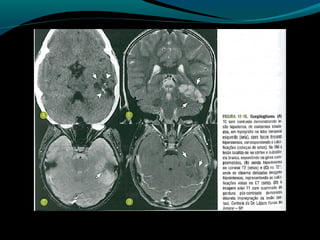

Glioblastoma

Maligno;

Origem astrocítica;

Grau IV;

60% dos astrocitomas;

15% das neoplasias intracranianas;

Mais frequente em adultos;

Sobrevida de 9 a 12 meses;

TC:

Geralmente supratentorial;

Infiltra substância branca;

Processo expansivo iso ou hipodenso de limites mal

definidos e necrose central;

Pode apresentar hemorragias;

Calcificações são raras;

RM:

Sinal heterogêneo em T1, T2 e FLAIR; (necrose, cistos,

hemorragia, neovascularização); mas predomina

hipointensidade em T1 e hiper em T2 e FLAIR;

Realce difuso e heterogêneo pelo Gd;